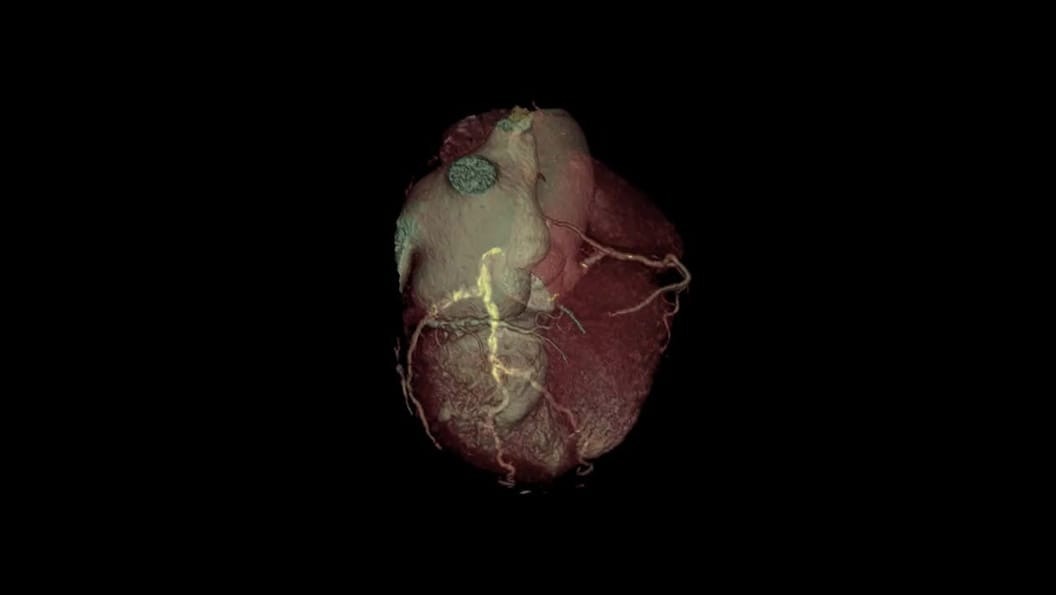

Expect exceptional results routinely—in a single beat

Complex CCTA becomes routine when advanced AI supports every image—streamlining and standardizing workflows even for challenging patients with unreliable ECG traces. See how Radiomed transformed its cardiac CT program to consistently deliver exceptional results.

SnapShot Freeze 2

Automated whole heart motion correction, SnapShot Freeze 2 is an intelligent motion correction algorithm designed for automated whole heart motion correction, including coronary artery, valves, myocardium, chambers, and the great vessels motions.